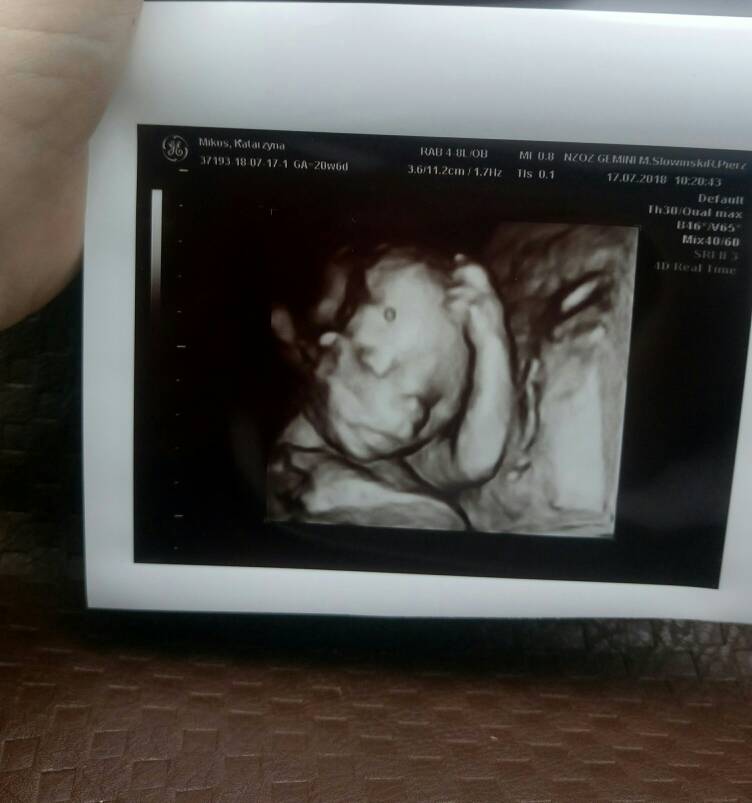

Super! Gratuluję 100% chłopca!

Śliczny!!!